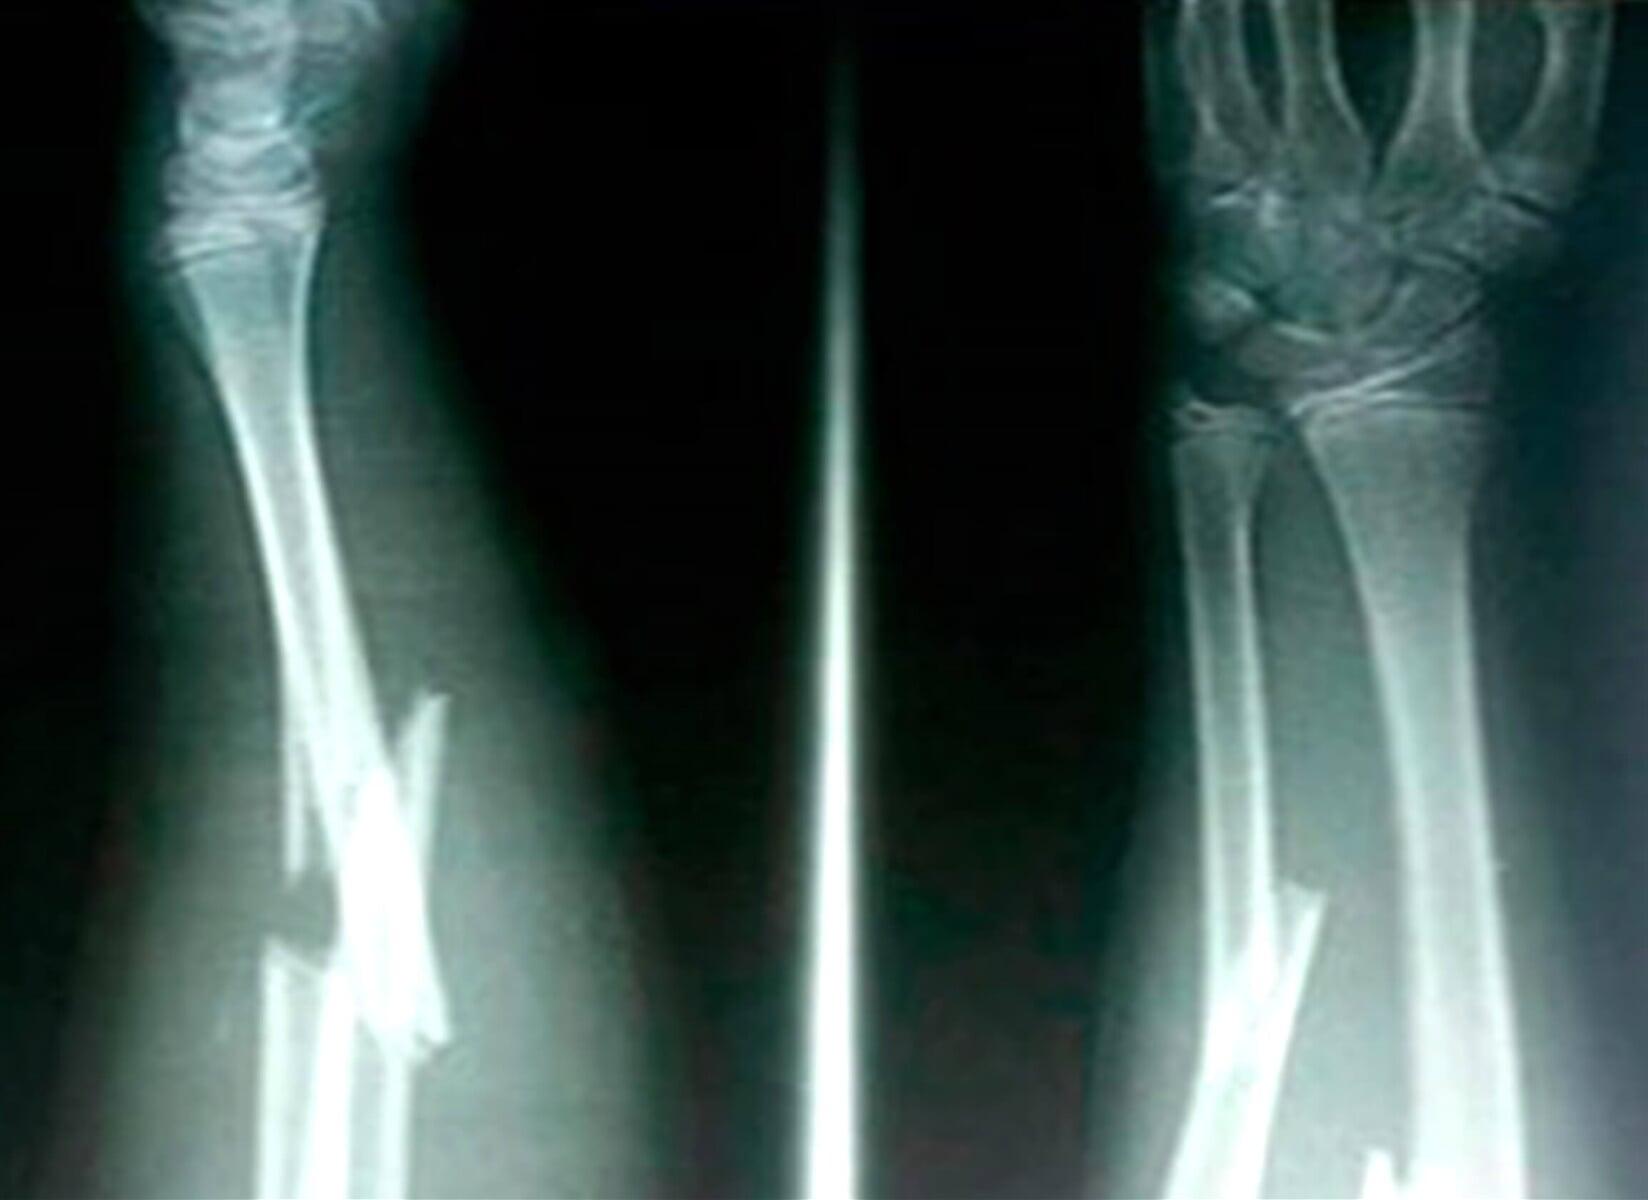

SANATORIO QUIROZ - TRAUMATOLOGÍA

• Traumatología